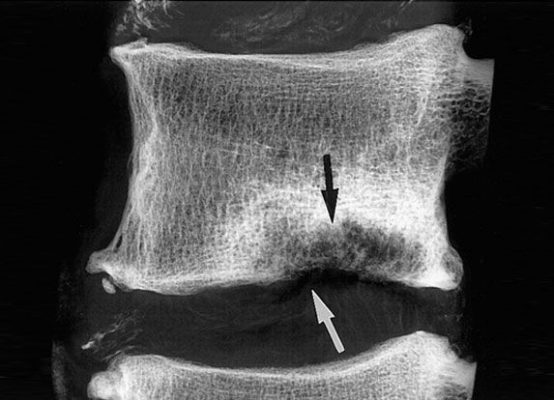

Грыжа Шморля — это разновидность межпозвоночных грыж. Такое заболевание нередко вызывает болевые ощущения,...

Межпозвоночная грыжа является заболеванием позвоночника, при котором деформированный позвоночный диск смещается, выходя...